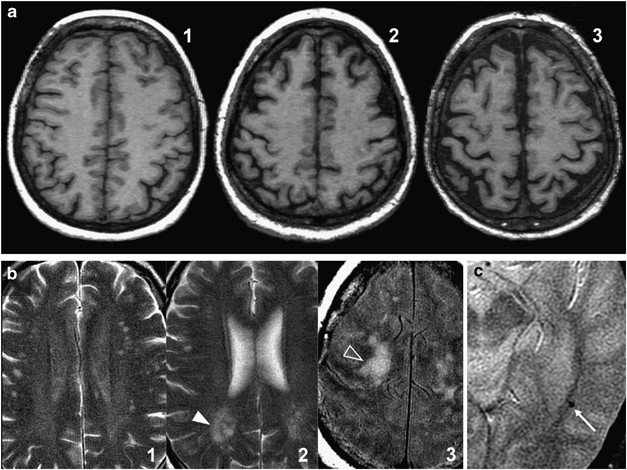

A single rater (JMGS), a neuroradiologist with 20 years of experience, assessed all images at a separate workstation, blinded to the clinical information. Ischemic burden (IB) was evaluated in the double-echo sequence. Following a simple scale,12 supratentorial age-related white matter (ARWM) changes were classified in one of four severity levels (Figure 1): 0, no ischemic lesions; 1, punctate lesions (focal lesions <10 mm in size, or groups of lesions <20 mm in diameter); 2, beginning confluent lesions (focal lesions 10–20 mm in diameter, or group of lesions >20 mm in diameter); and 3, confluent lesions (single lesions or confluent areas of hyperintensity >20 mm in diameter), in the frontal, parieto-occipital and temporal lobes. In the basal ganglia, IB was classified in four severity levels (0, no ischemic lesions; 1, one lesion >5 mm; 2, two or more lesions >5 mm; and 3, confluent lesions). All lobar ischemic scores plus the basal ganglia ischemic scores plus the posterior fossa score (same scale as supratentorial white matter) made up the total IB, for a maximum score of 27.

(a) Atrophy scoring. Axial reformatted 3-mm thickness T1-weighted images. From left to right are images from three different patients showing no atrophy (1), some atrophy (2) and substantial atrophy (3). No patient in our sample met the criteria for end-stage atrophy. (b) Ischemia scoring. Axial long TR double-echo images. From left to right are images from three different patients with punctate lesions (1), beginning confluent lesions (2, white arrowhead) and confluent lesions (3, open arrowhead). (c). Microbleeds. Axial gradient-echo T2-weighted image. Tiny hypointense brain lesion (arrow) corresponding to a small hemorrhage.

Global cortical atrophy analysis was carried out with a reported simple scale.13 Atrophy scoring was mainly carried out by means of 3-mm thickness, reformatted, axial SPGR-T1W images, although they were interactively assessed with sagittal and coronal reconstructions. Each subject was assigned to one of the four global severity steps according to the Pasquier scale (0, no atrophy; 1, some atrophy; 2, substantial atrophy; and 3, end-stage atrophy) (Figure 1). The presence or absence of brain microbleeds was assessed in gradient-echo T2W images. A positive diagnosis was considered when very hypointense, round, parenchymal foci >2 mm and <10 mm were identified (Figure 1).14 When appropriate, confounding flow voids were distinguished using the axial, double-echo, long TR FSE images for comparison.